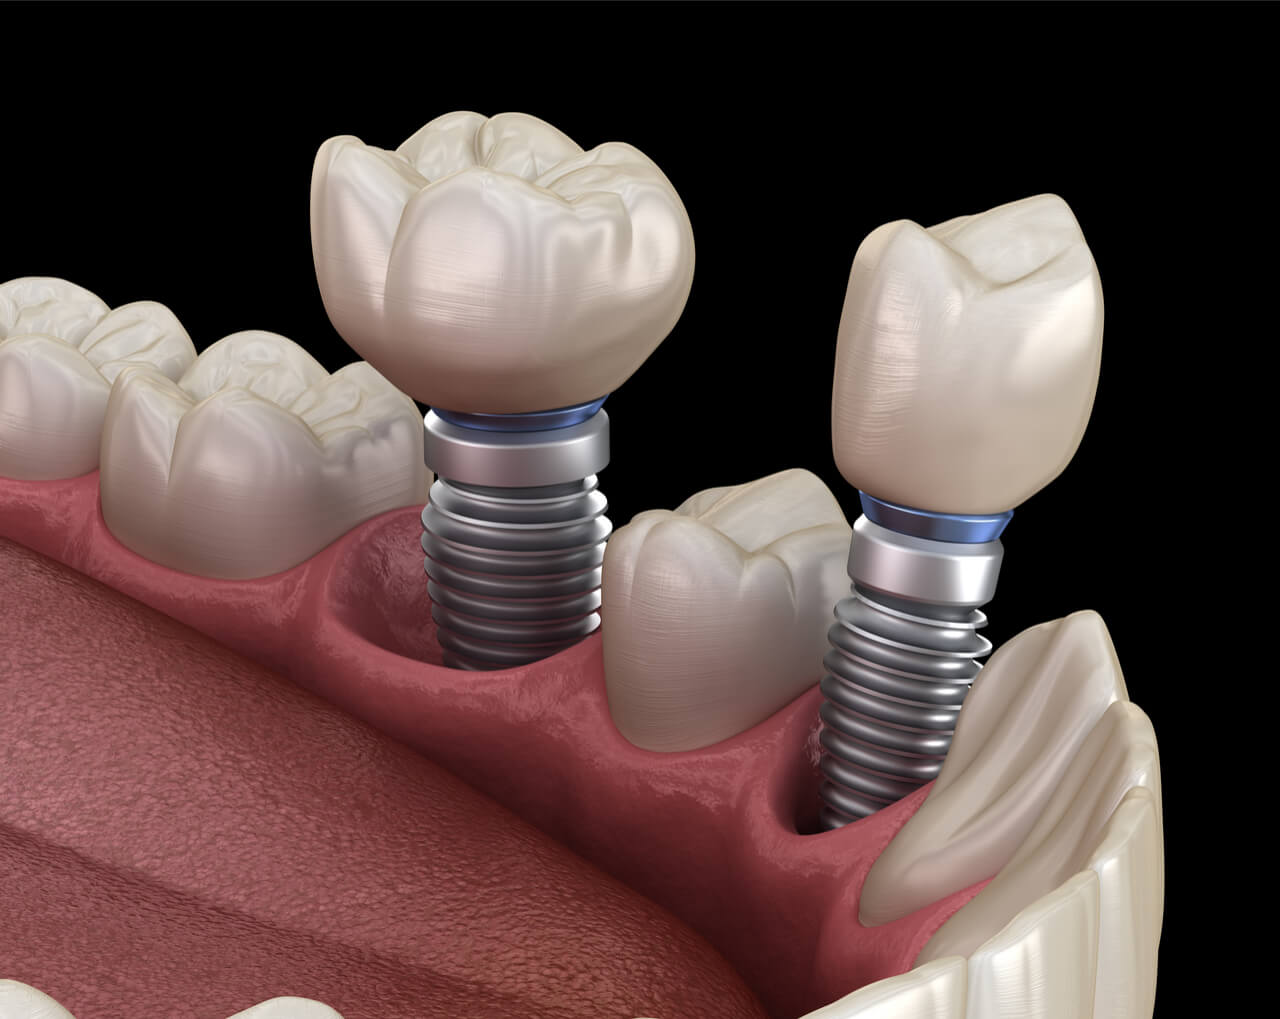

Современные коронки на зубные импланты: виды и фото-примеры